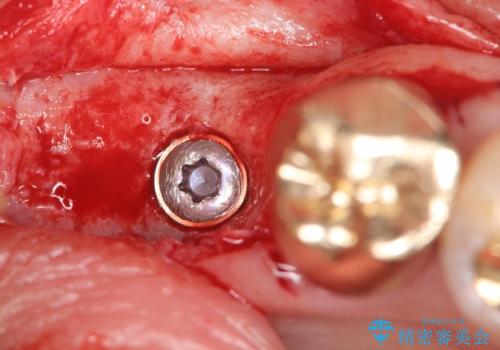

残根状態の歯を抜歯後、抜歯窩の治癒を待ちインプラントを埋入しています。

アバットメントの材質は咬合力を考慮しチタン合金にしました。